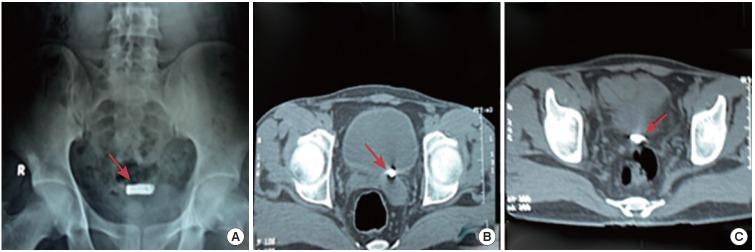

A total of 49 foreign bodies were retrieved from patients' urinary bladders during the study period. The patients ranged in age from 11 to 68 years. Thirty-three patients presented with complaints of haematuria (67.3%), 29 complained of frequency of urination and dysuria (59.1%), and 5 patients reported pelvic pain (10.2%). The circumstances of insertion were iatrogenic in 20 cases (40.8%), self-insertion in 17 cases (34.6%), sexual abuse in 4 cases (8.1%), migration from another organ in 4 cases (8.1%), and assault in 4 cases (8.1%). Of the foreign bodies, 33 (67.3%) were retrieved by cystoscopy, while transurethral cystolitholapaxy was required in 10 patients (20.4%), percutaneous suprapubic cystolitholapaxy was performed in 4 patients (8.1%), and holmium laser lithotripsy was performed in 2 patients (4.08%).

在研究期间,共从患者膀胱中取出49个异物。患者年龄在11岁至68岁之间。33例患者出现血尿症状(67.3%),29例患者有尿频和尿痛症状(59.1%),5例患者报告有盆腔疼痛(10.2%)。置入情况为医源性20例(40.8%),自行置入17例(34.6%),性虐待4例(8.1%),从其他器官迁移4例(8.1%),袭击4例(8.1%)。其中33个异物(67.3%)通过膀胱镜取出,10例患者(20.4%)需要行经尿道膀胱结石碎石术,4例患者(8.1%)进行了经皮耻骨上膀胱结石碎石术,2例患者(4.08%)进行了钬激光碎石术。